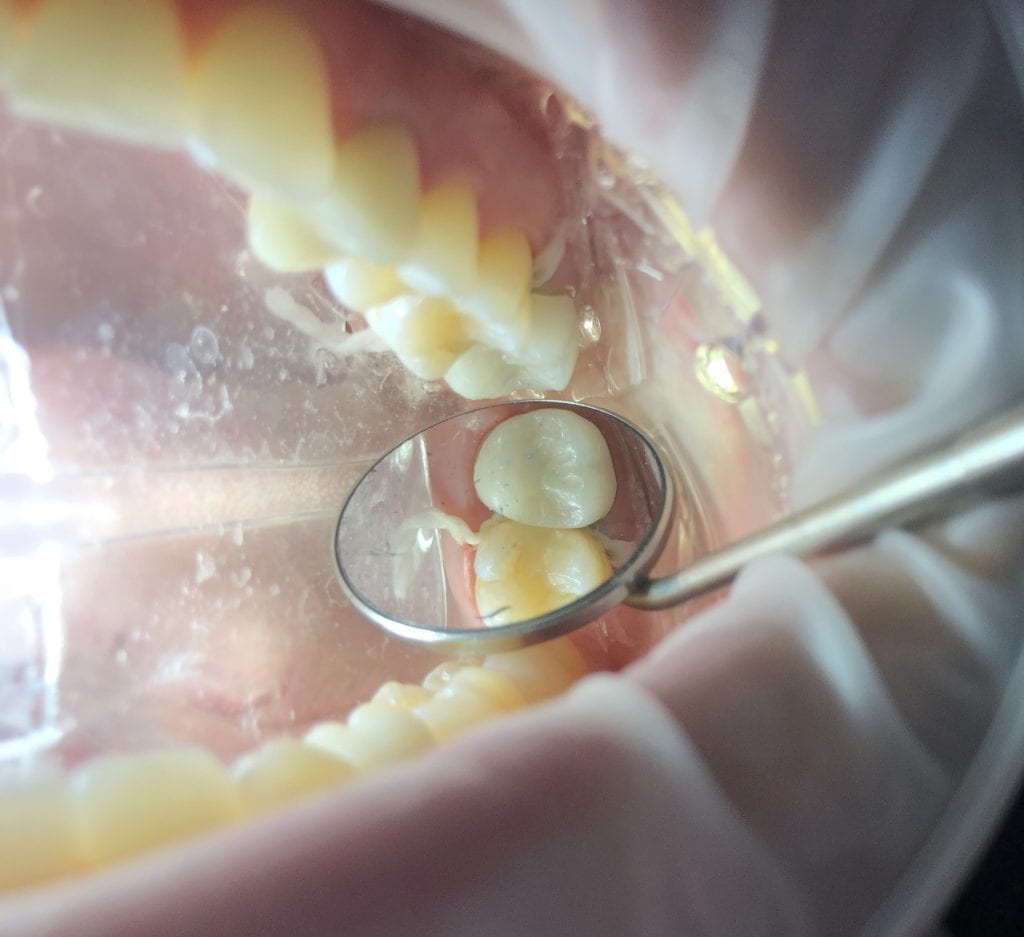

It was a long struggle to find margins with the Omnicam and after 4 years it was sold. The margin definition and resolution never reached an acceptable level. After seeing margins from high resolution scans by the Medit and defining them in exocad, it completely validated that we shouldn’t settle for anything less than the highest standard. This is an scan performed on a upper second molar with tough access, replacing a failing crown.